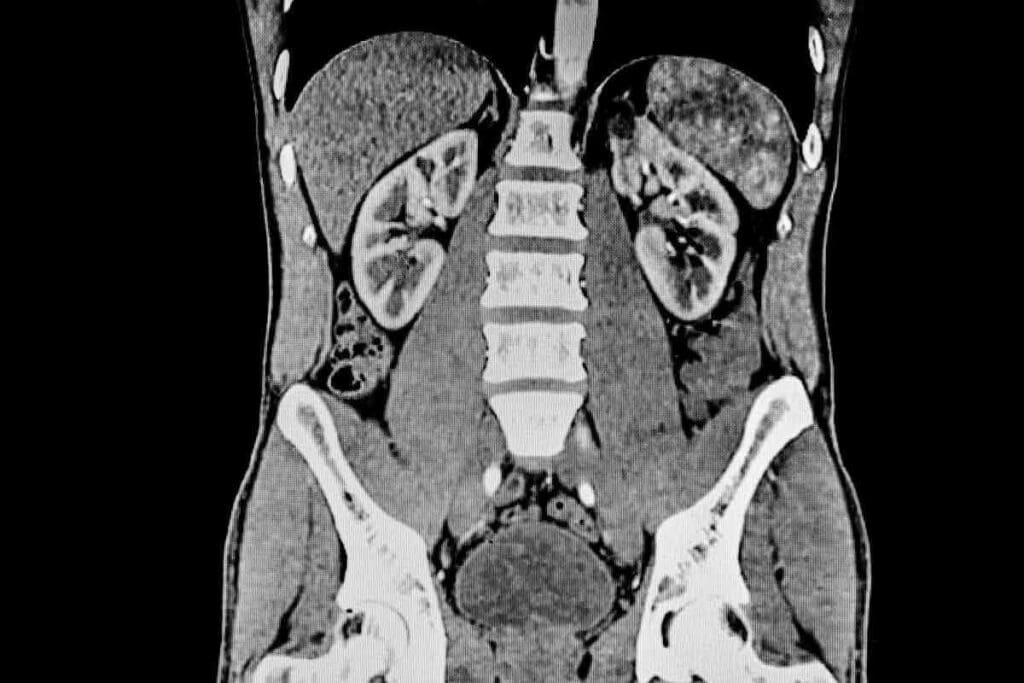

Normal Kidney Appearance on CT

A normal kidney CT scan shows kidneys that are the right size and shape. You can see the renal cortex and medulla clearly. The renal pelvis and calyces are also well-defined. The scan also shows the tissues and blood vessels around the kidneys.

Common Abnormalities on Kidney CT Scan

CT scans are great at finding different kidney problems. Some common issues include:

- Kidney cysts: Fluid-filled sacs that can be simple or complex

- Kidney stones: Hard mineral deposits that can cause pain and block urine flow

- Tumors: Benign or malignant growths that need more checking

- Pyelonephritis: Infection or inflammation of the kidney

- Hydronephrosis: Swelling of the kidney due to urine buildup

How CT Scans Help Detect Kidney Disease

CT scans are key in finding and tracking kidney disease. They can spot:

| Condition | CT Scan Findings |

| Kidney Damage | Scarring, atrophy, or irregular kidney contours |

| Chronic Kidney Disease | Reduced kidney size, cortical thinning, or cystic changes |

| Kidney Cancer | Masses or tumors within the kidney |

CT scans give detailed images of the kidneys. This helps doctors make accurate diagnoses and plan the best treatments. Knowing what your CT scan might show can help you understand your care better and make informed health choices.